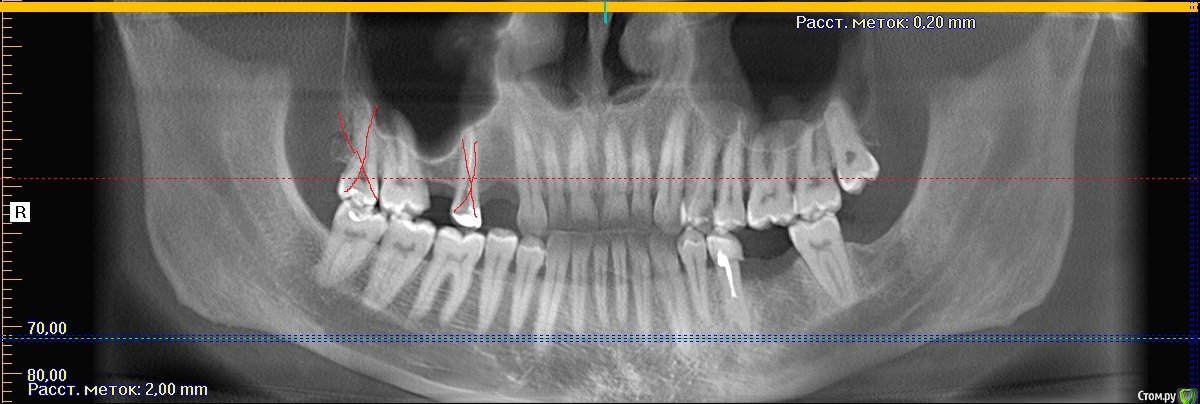

shurkne Опубликовано 11 апреля, 2015 Поделиться Опубликовано 11 апреля, 2015 Здравствуйте!сверху справа остались 1.1 1.2 1.3 1.7Планирую ставить имплантыесть несколько вопросов1. Ставть три импланты или мост на двух?2. 1.7 сдвинулся к центру и стоит немного криво..что с ним делать?3. зуб 4.5 поднялся выше остальных что с ним делать? Ссылка на комментарий

red_butler Опубликовано 11 апреля, 2015 Поделиться Опубликовано 11 апреля, 2015 1. Можно и два и три2. По снимку смещение не критичное3. Нужно смотреть очно Ссылка на комментарий

red_butler Опубликовано 11 апреля, 2015 Поделиться Опубликовано 11 апреля, 2015 то есть в имеющуюся так сказать "щель" влезут три импланта ?Я располагаю только панорамной реконструкцией из Кт, для принятия решения нужен очный осмотр или фотографии. Лично я бы ограничился 2 имплантами. 1 Ссылка на комментарий